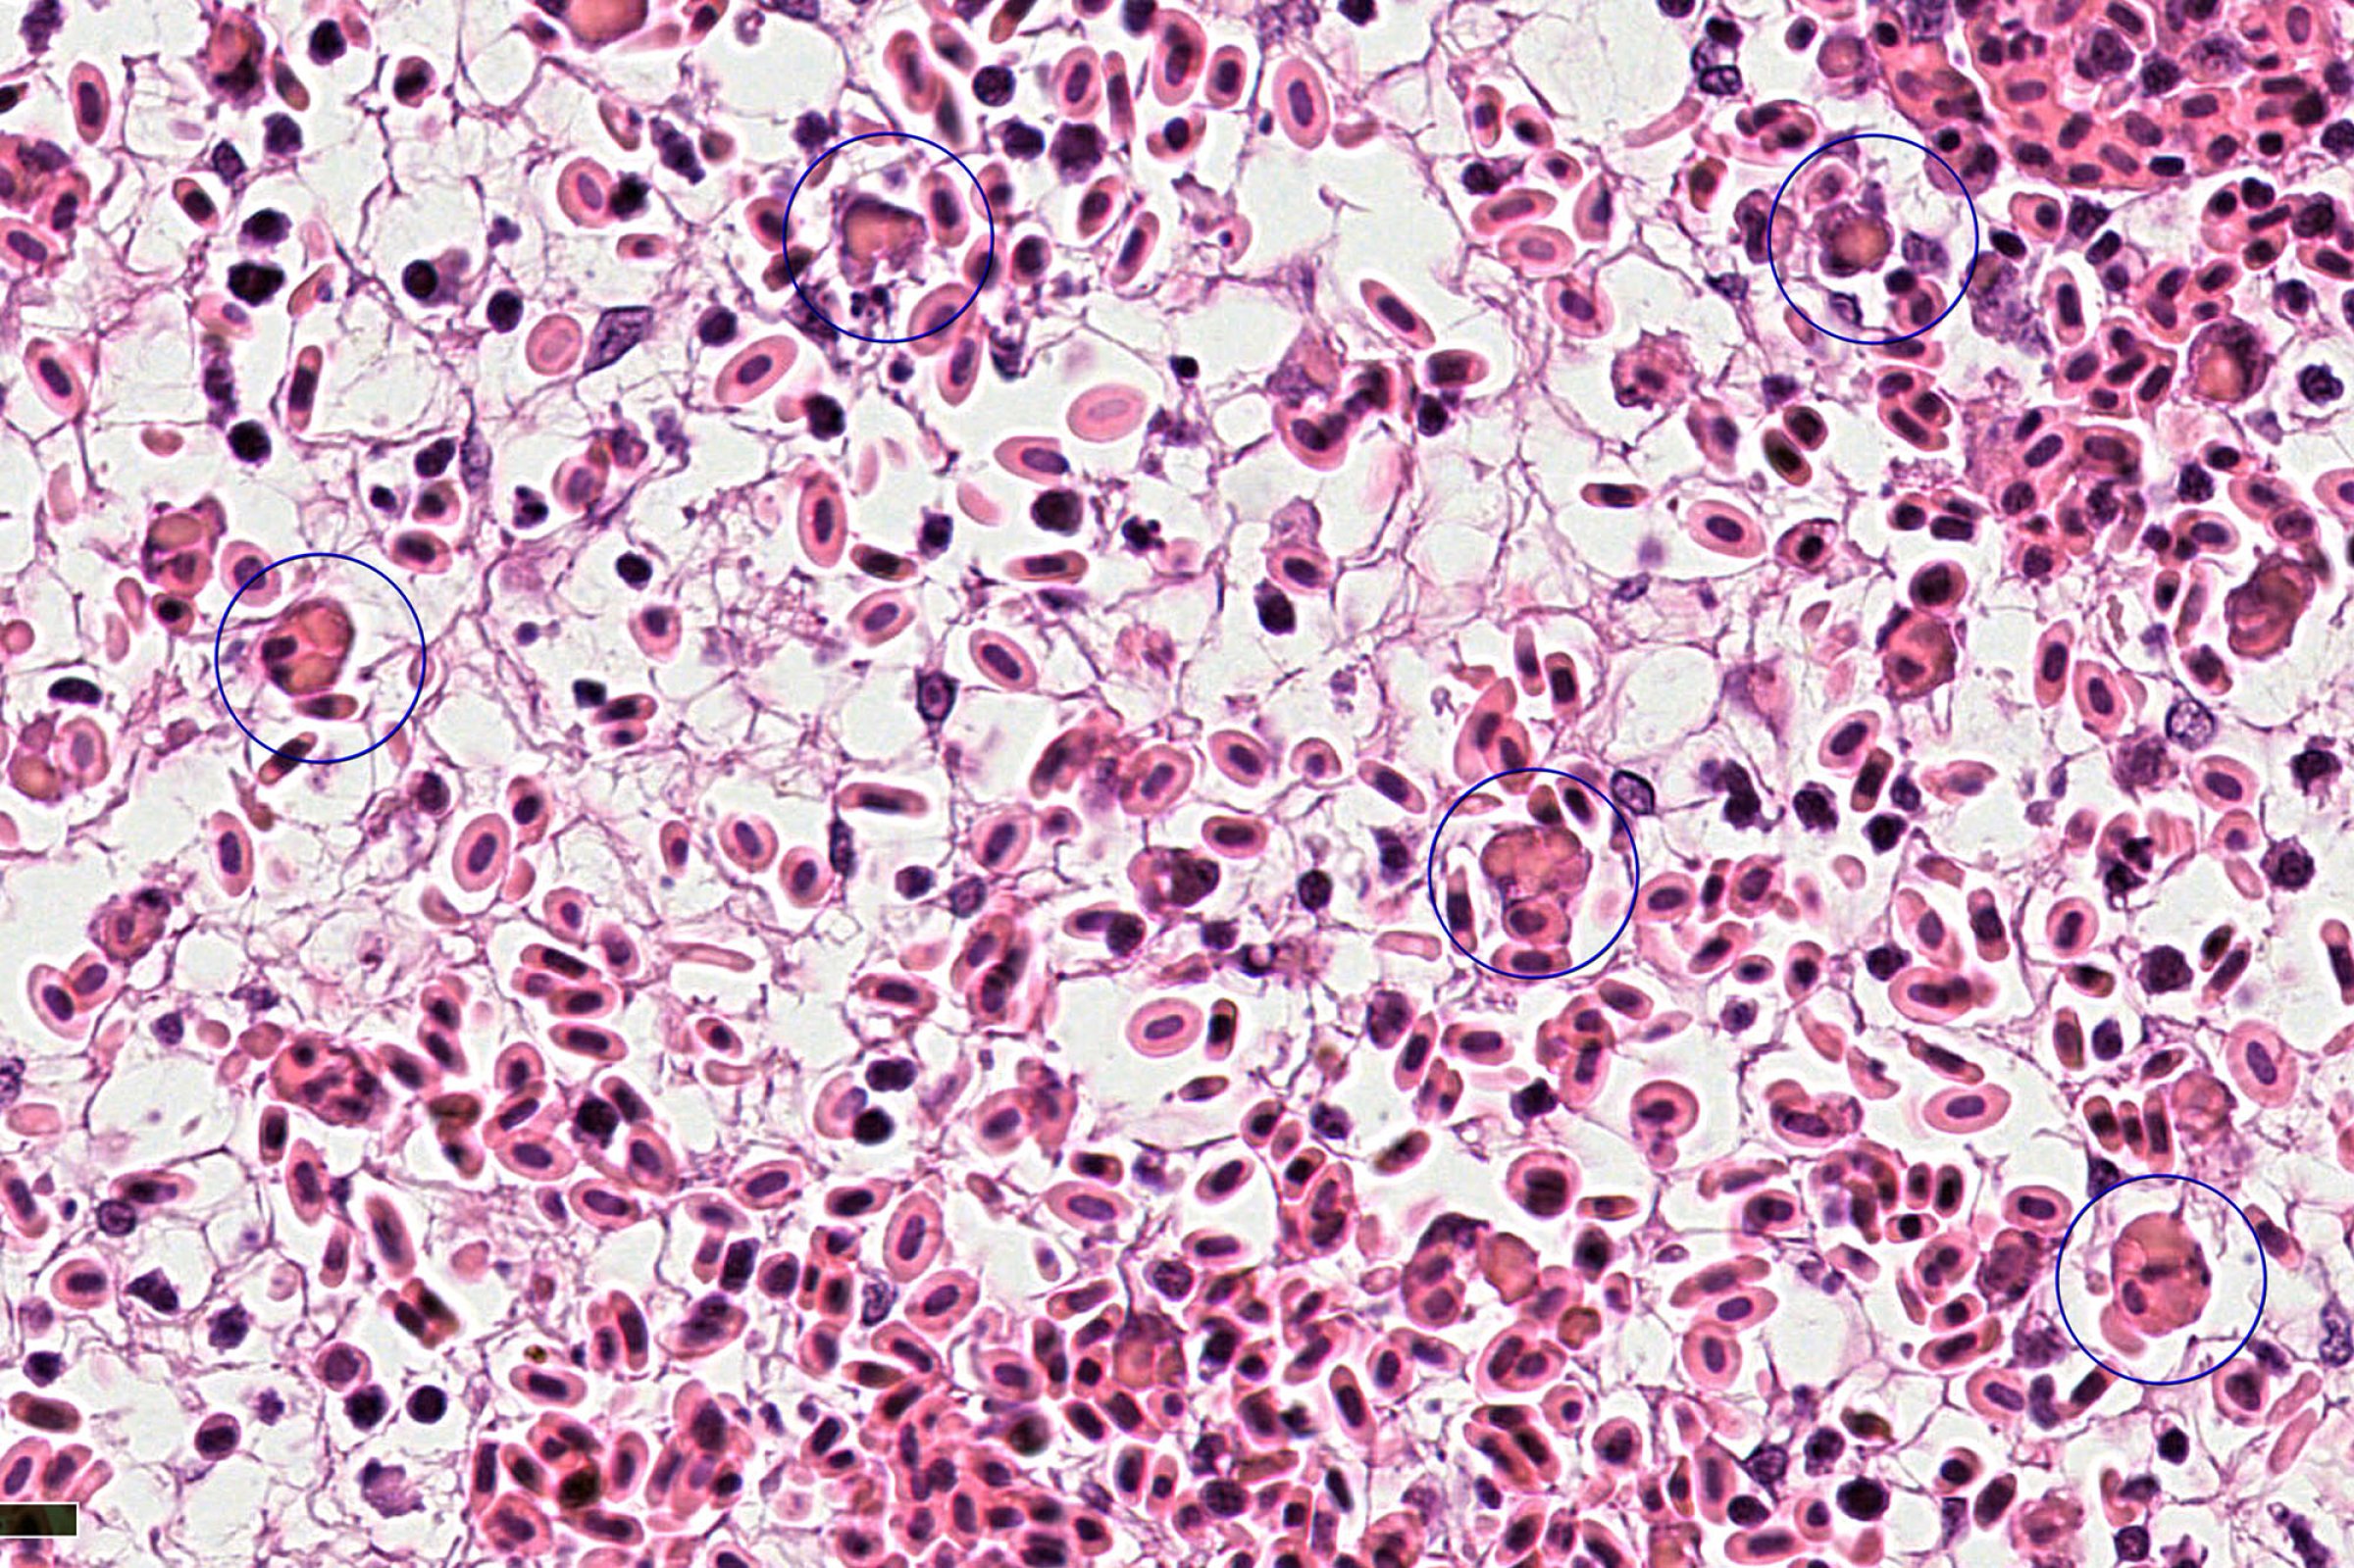

Infeksiøs lakseanemi (ILA) er som kjent en alvorlig, smittsom virussykdom hos atlantisk laks. ILA er meldepliktig både i Norge og internasjonalt. Veterinærinstituttet er referanselaboratorium for ILA, både nasjonalt og internasjonalt for OIE (Verdens dyrehelseorganisasjon